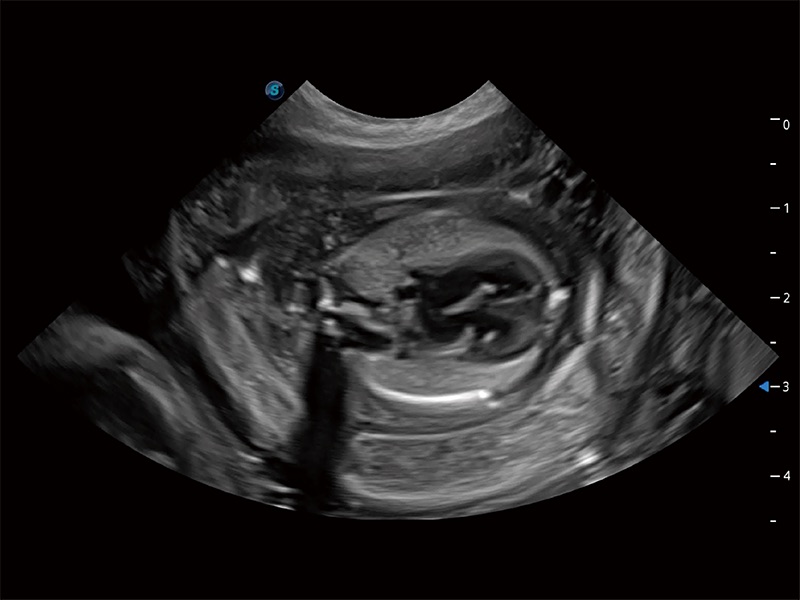

极大提升超低速微细血流的检出能力,同时更精准地滤除软组织和超声信号,为兽用医生提供以往无法通过常规血流获得的疾病诊断信息。

在传统二维血流成像的基础上,呈现血流的立体感,具有动感的生命力之美。即便是微小的血管也能轻松应对,提高了血流的视觉敏感性。